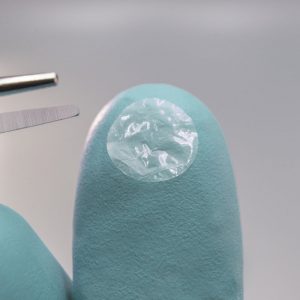

• Textured surface facilitates ease of handling and placement

• Symmetric graft allows either side to be placed in contact with ocular surface

Remove graft using sterile gloves or smooth tip forceps.

Apply the graft over the intended site.